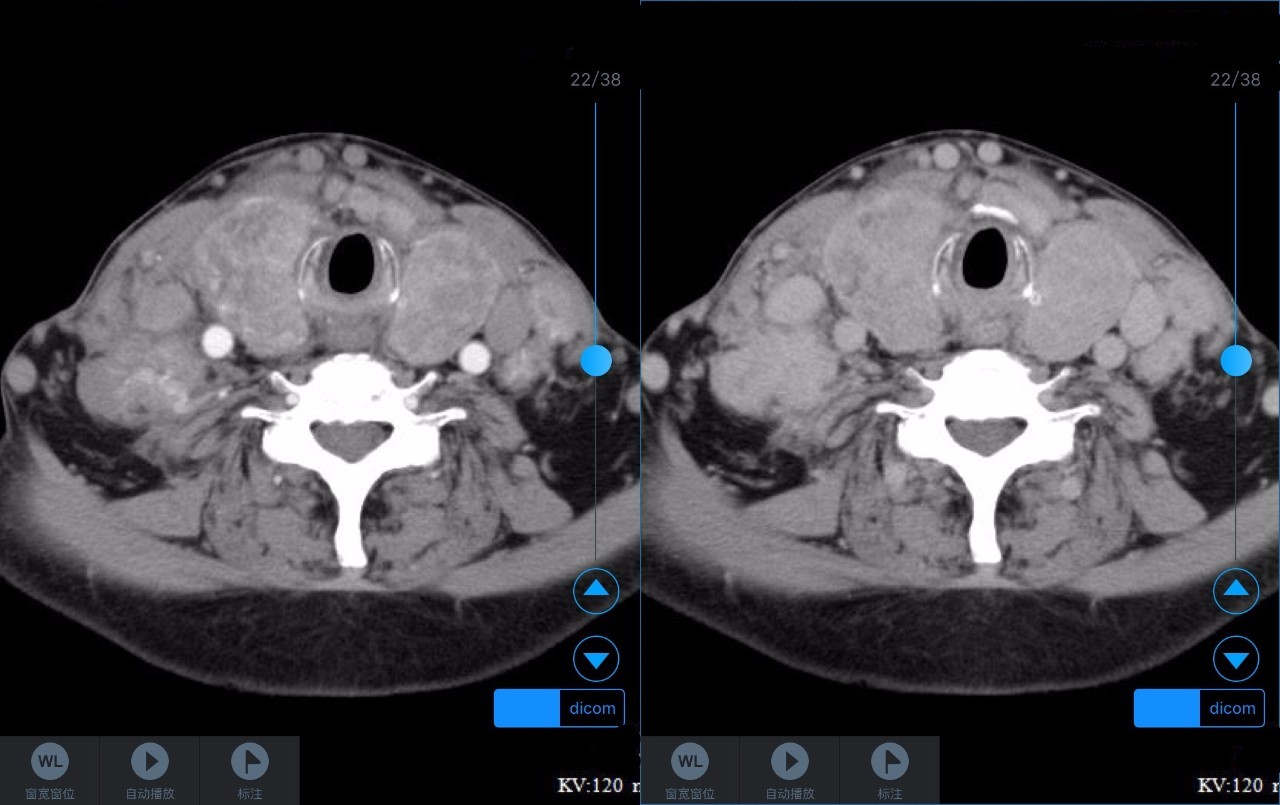

▼患者CT平扫(右)及增强CT(左)检查报告资料

Z主任 甲状腺肿大,内见弥漫多发结节,界限不清,甲状腺包膜毛糙。双侧颈部、锁骨上、纵隔多发肿大淋巴结,病变均强化明显,密度不均,边缘毛糙,考虑甲状腺恶性肿瘤伴多发淋巴结转移,或甲状腺内也是转移瘤。Castleman病多灶者少见,一般病变边缘光整,也不会累及甲状腺。建议穿刺活检。 C主任 双侧甲状腺肿大,密度不均,不均匀强化,甲状软骨未见明显骨质破坏气管右侧壁受压;双侧颈部多发肿大淋巴结,不均匀强化;考虑为甲状腺恶性占位性病变伴双侧颈部淋巴结转移,建议组织学进一步检查。 声明:以上资料均来自和缓名医平台的真实案例,为保护用户隐私,均用化名代替。资深医师Z咨询反馈